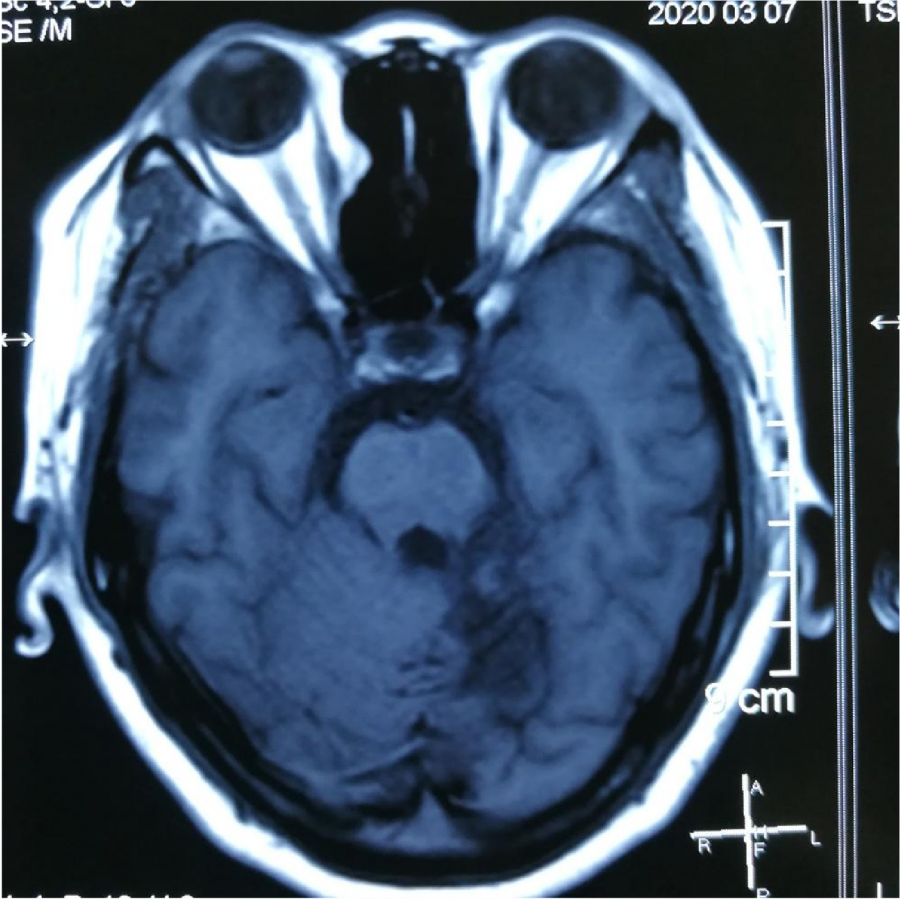

⼊院CT显⽰:桥脑旁有出⾎

MR显⽰桥脑左侧⾼信号影

小脑及脑⼲受累